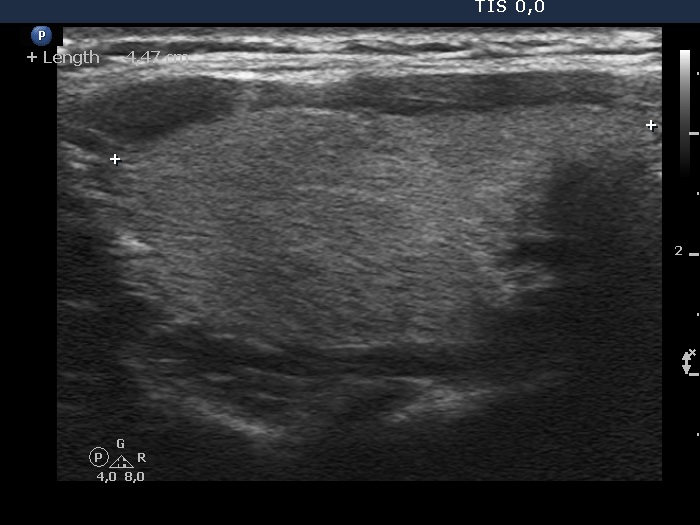

Initial examination (first row of images):

Clinical presentation: A 33-year-old woman was referred for evaluation of complaints suggesting hypothyroidism, including 12 kg weight gain, fatigue.

Palpation: Both lobes were palpable and not firm.

Laboratory examination: TSH 0.79 mIU/L, anti-TPO < 28 IU/mL.

Ultrasonography: The thyroid was echonormal and intact.